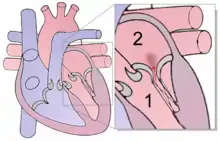

Echocardiogram

|

|

| Severe MR | Legend |

| 1 Left atrium (LA) – 2 MR Jet, LV Left ventricle – RV Right ventricle – RA Right atrium | |

An echocardiogram is commonly used to confirm the diagnosis of MR.[16] Color doppler flow on the transthoracic echocardiogram (TTE) will reveal a jet of blood flowing from the left ventricle into the left atrium during ventricular systole. Also, it may detect a dilated left atrium and ventricle and decreased left ventricular function.[6] A transesophageal echocardiogram can give clearer images if needed as the back of the heart can also be viewed.[17]